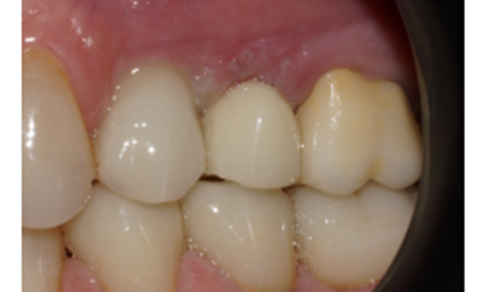

Após cinco meses, a paciente retornou da viagem do exterior, o provisório foi removido e um novo escaneamento foi realizado, copiando assim, o perfil de emergência alcançado através do provisório. As informações foram enviadas para o laboratório e o provisório foi reinstalado (Figuras 15, 16, 17, 18, 19 e 20).

No laboratório foi realizado um novo projeto e o elemento 25 foi fresado em zircônia multilayer na cor A2. Em seguida, maquiado para deixá-lo semelhante aos dentes adjacentes.

Na consulta seguinte a coroa final foi instalada e aparafusada com o parafuso Torx, e o orifício foi restaurado com resina fotopolimerizável. Foi realizada uma radiografia final e a paciente foi remarcada para retornar em seis meses para consulta de controle.